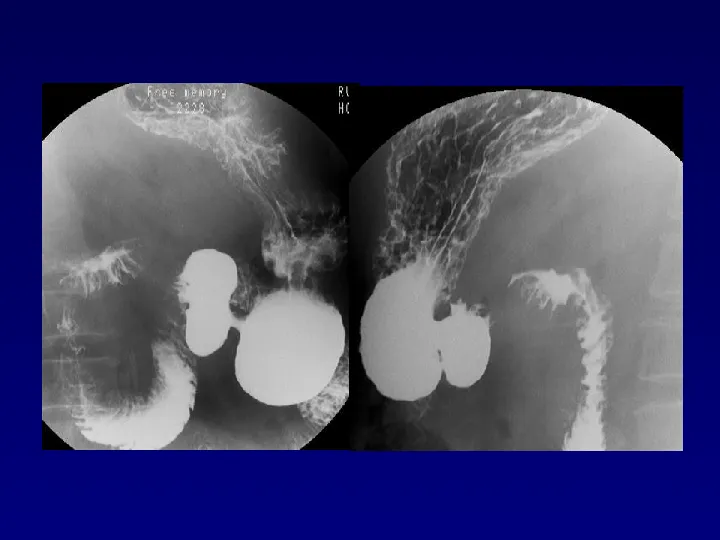

>【影像PPT】胃肠道钡餐检查的操作规范

【影像PPT】胃肠道钡餐检查的操作规范